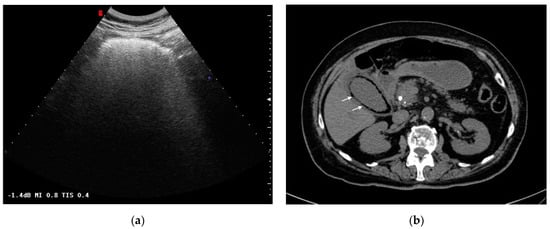

Figure 4.

Gallbladder perforation: transmural defect of the gallbladder wall (black arrow) with pericholecystic effusion (head arrows) and perihepatic peritoneal collection, suggestive of biliary peritonitis (white arrows).